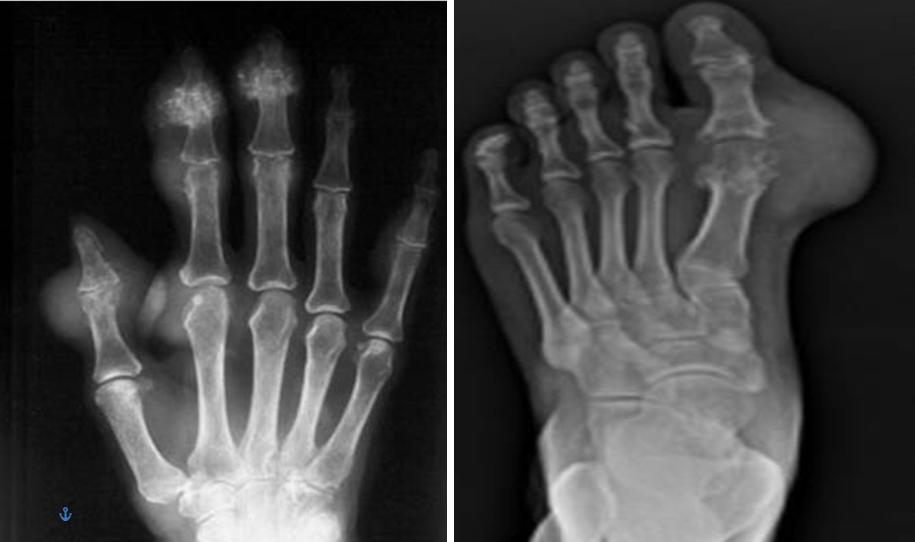

双腕、手及双足部分关节周围可见软组织不对称结节肿胀,密度稍增高;部分关节面下及边缘见部分囊状、穿凿样骨质破坏。

影像学检查对诊断痛风,评价病情有很大帮助,该患者双源CT,超声及X线均显示典型痛风改变,临床医生应合理应用这些敏感特意的影像学手段诊断、管理痛风。